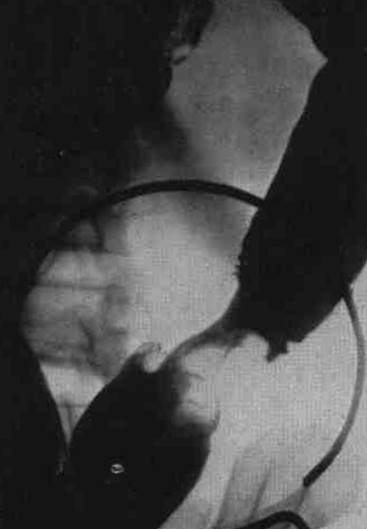

Вопросы к рис. 1:

1) Что такое ирригоскопия?

2) Назовите основной рентгенологический признак рака сигмовидной кишки на прицельной рентгенограмме при ирригоскопии. Покажите его.

Рис. 1

Ответы:

1) Ирригоскопия – метод рентгенологического исследования толстой кишки путем ретроградного (с помощью клизмы) заполнения ее рентгенконтрастным веществом (взвесью сульфата бария).

2) На прицельной рентгенограмме сигмовидной кишки определяется циркулярное сужение ее, контуры суженного участка неровные, определяется «дефект наполнения».